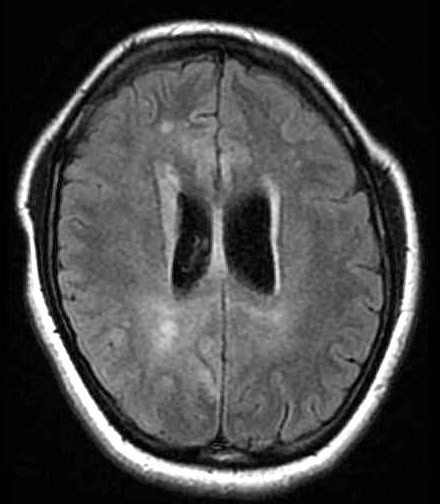

| Fem. 17a. |

| Nódulo sólido homogêneo preenchendo o III ventrículo, com limites precisos, com hipossinal em T1 e hipersinal em T2 e FLAIR, que se impregna por contraste paramagnético. Lesão menor implantada no assoalho do IV ventrículo provavelmente representa disseminação por via liquórica. |

| AXIAIS, FLAIR | T2 | |

| F. 17a. Tumor teratóide rabdóide atípico de III ventrículo. RM | HE | VIM, GFAP | HHF35, desmina, 1A4 | AE1AE3, EMA |